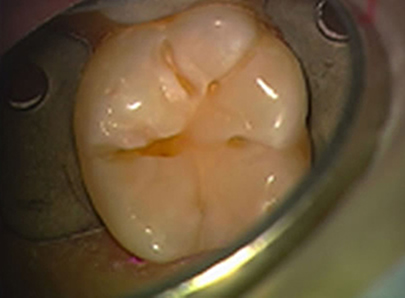

Erweiterte Fissurenversiegelung und Mikrofüllung

nach der Präperation